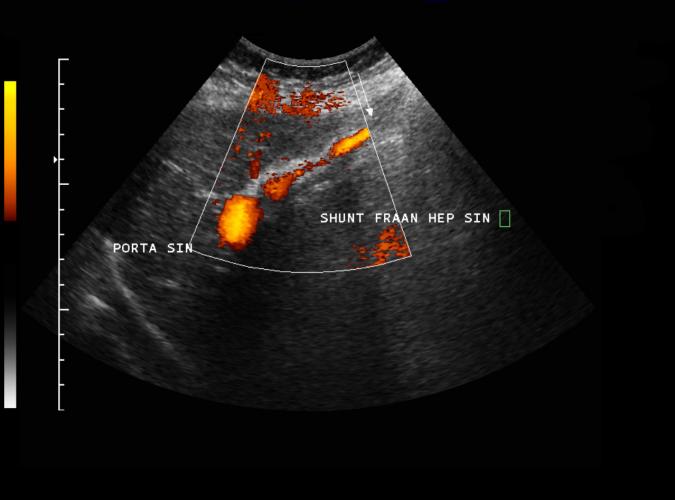

Long. vänster leverlob. Med power-Doppler påvisas shuntning igenom vena umbilicalis i patienten med biliär cirrhos.(3a,b,d)